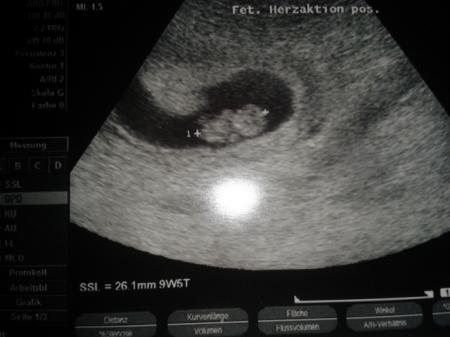

Noch mal ein Versuch....

Bild zu